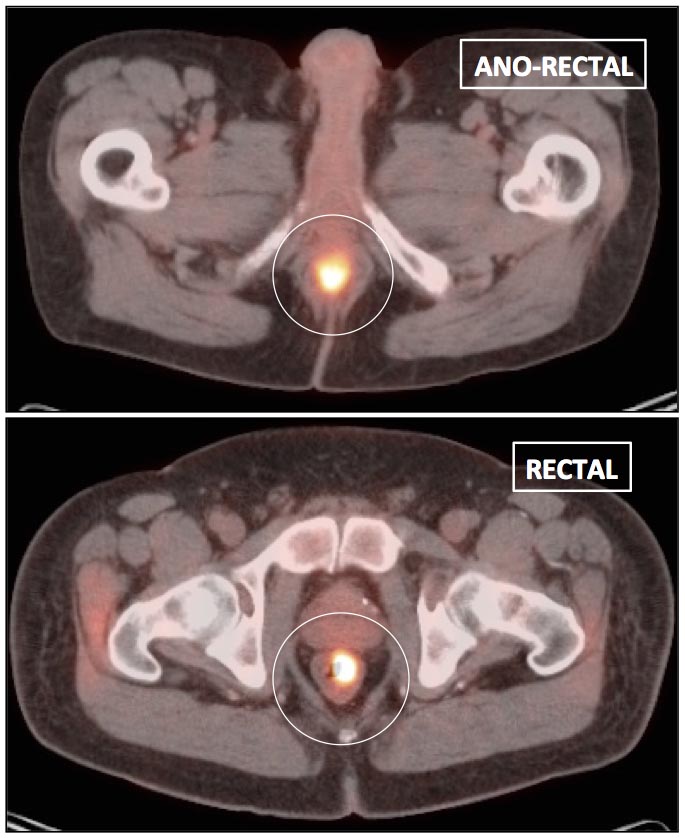

Focal intense uptake in the ano-rectal region is a very common finding. It is considered normal in the absence of an associated soft tissue abnormality. It is often attributed to hemorrhoidal inflammation.

Be careful to not confuse ano-rectal uptake (typically representing hemorrhoidal inflammation) with rectal uptake (often malignancy).